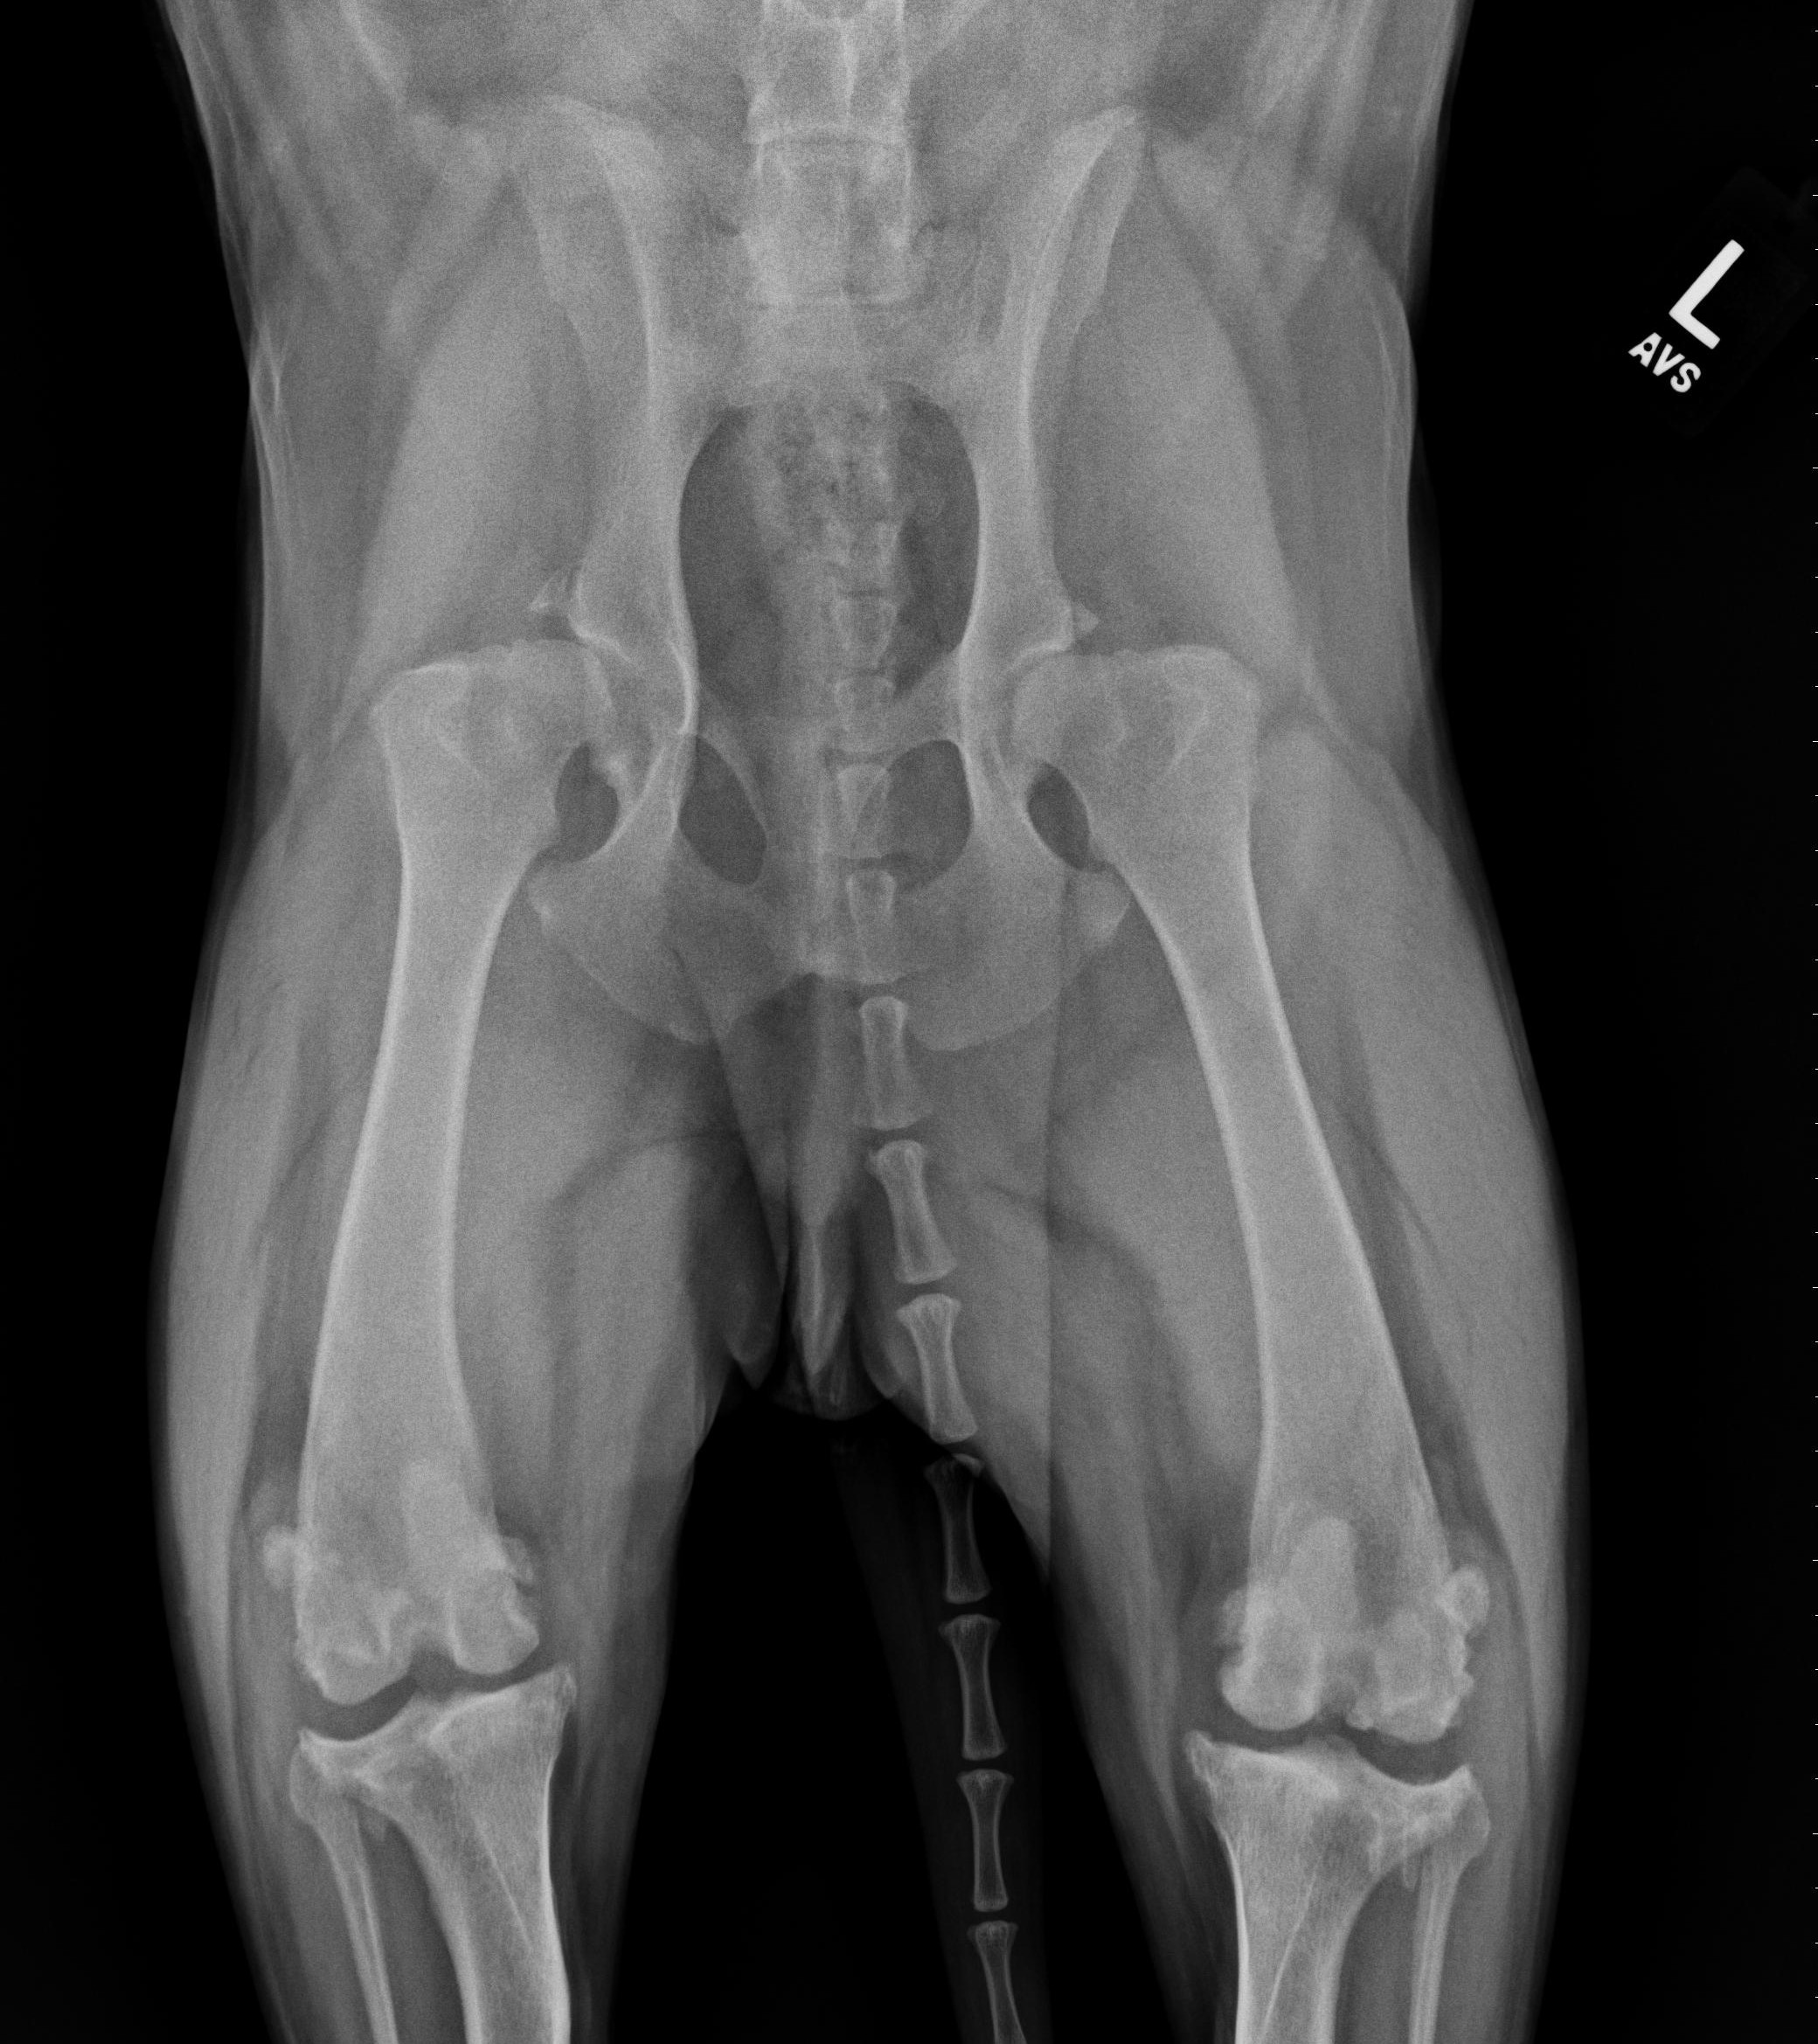

Scooter is a 5 yr old Labrador Retriever that presented for lameness in both hind limbs. His history was such that he was lame in the left hind limb about a year ago and had a previous surgical procedure to address the CrCL performed, to which he responded well early on but became increasingly lame again in the leg and then developed a right hind limb lameness in addition. The procedure previously performed on the left stifle (knee) was not documented and no radiographic implants were used in or around the stifle. Also, Scooter has a chronic history of hip dysplasia and osteoarthritis in both hips to compound his issues.

Scooter could walk with assistance, however really struggled in both hind limbs to ambulate. Also, you could see Scooter shifting his weight to his front legs, which is a very classic feature for dogs with CrCL ruptures that affects both stifles. Our physical exam revealed that both (left and right) CrCL were ruptured and we highly suspected bilateral meniscal injuries/tears. While some discomfort could be elicited from manipulation of his hips, the majority of his discomfort and inability to walk was from his CrCL ruptures and meniscal tears.

Right knee – note the joint swelling, arthritic changes, and forward movement of the tibia in relation to the femur.

Left knee – note the joint swelling, arthritic changes, and forward movement of the tibia in relation to the femur.